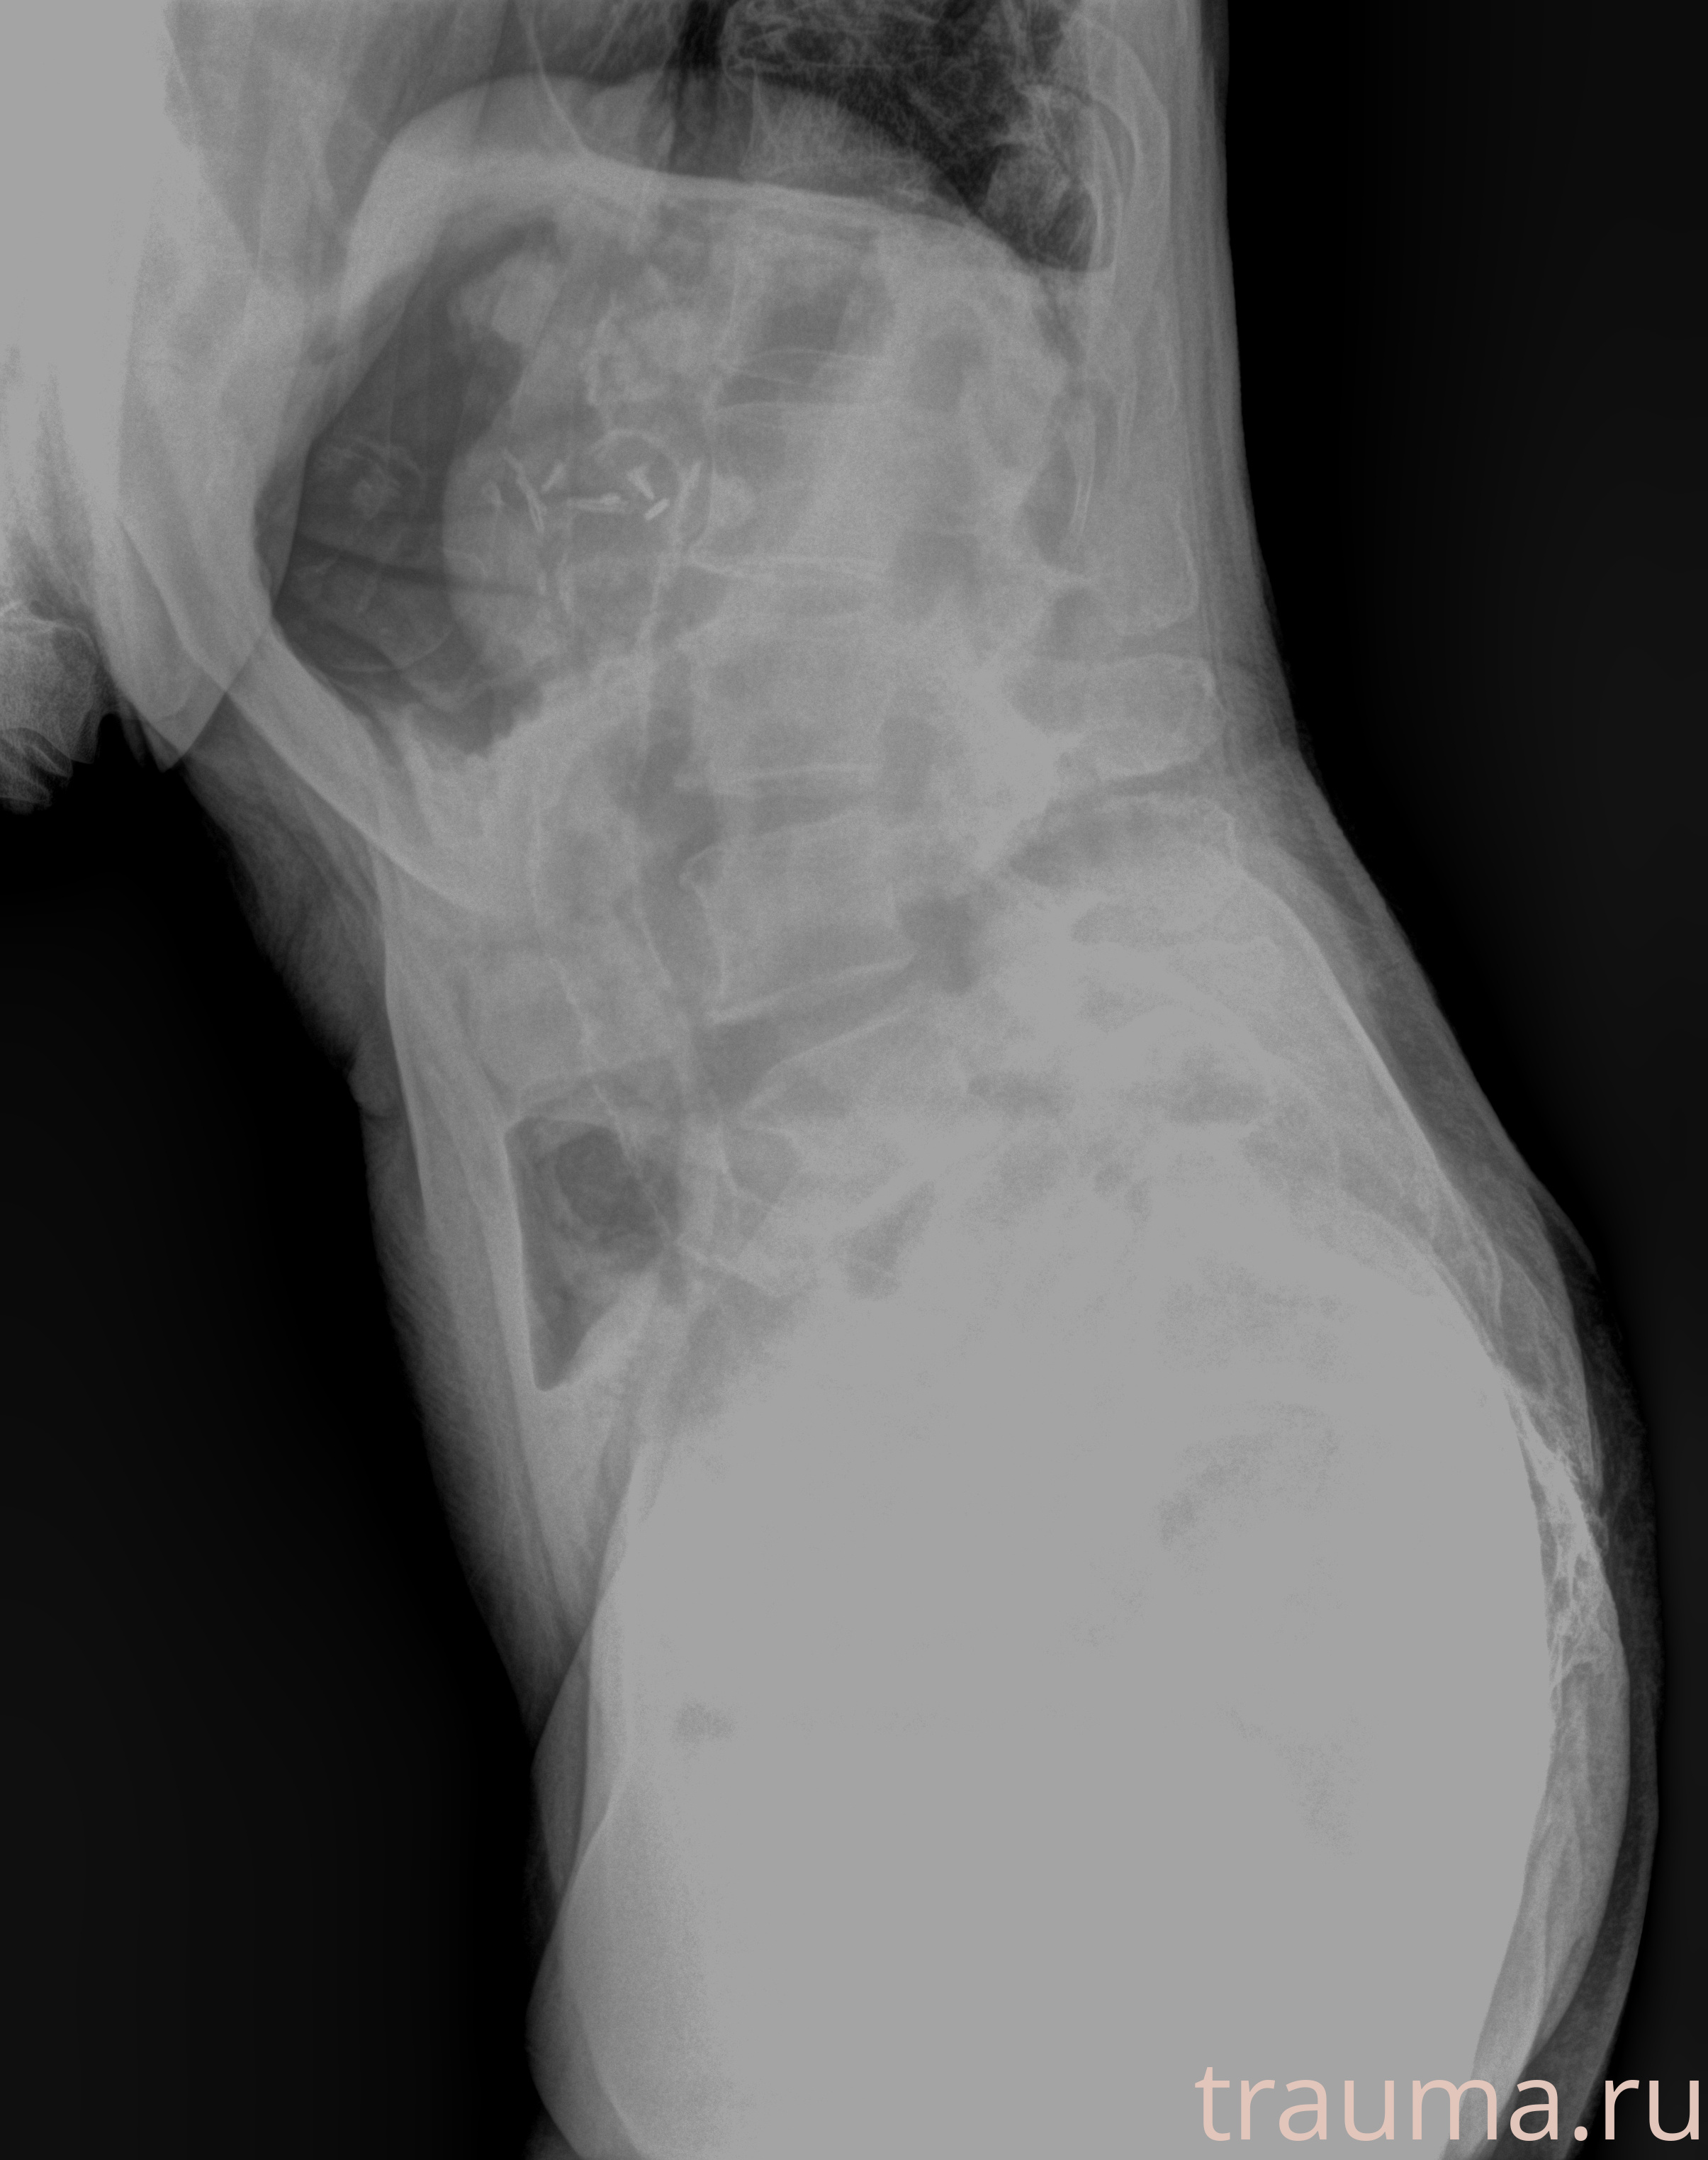

Рентгенограммы

Рентген на дому: по вашему адресу приезжает врач-рентгенолог, травматолог-ортопед с мобильным рентгеновским аппаратом, проводит диагностику травмы или заболевания, делает необходимые рентгенограммы, дает рекомендации по дальнейшему лечению. Получить качественные снимки в домашних условиях возможно благодаря уникальной методике, разработанной МосРентген Центром для института  Склифосовского

при переломе шейки бедра и пневмонии от компании МосРентген Центр - партнера Института имени Склифосовского